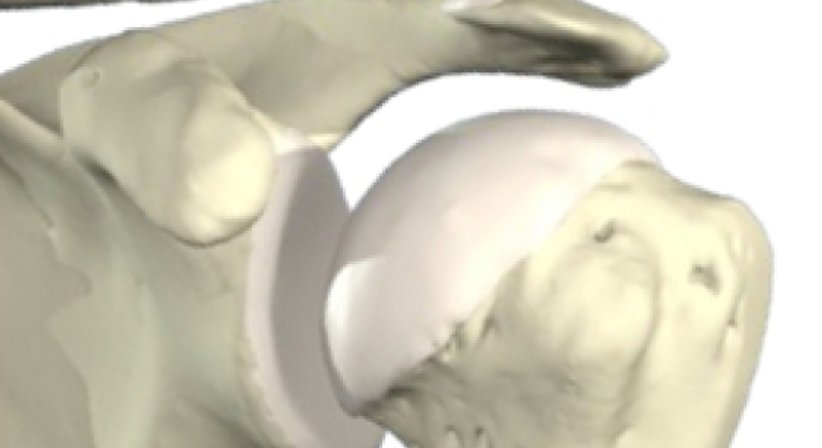

Die Schulter ist das komplexeste Gelenk des menschlichen Körpers. Bänder, Muskeln, mehrere "Zwischengelenke",Schleimbeutel,und Sehnen ermöglichen in kompliziertem Zusammenspiel Beweglichkeit in allen 3 Ebenen de Raumes.